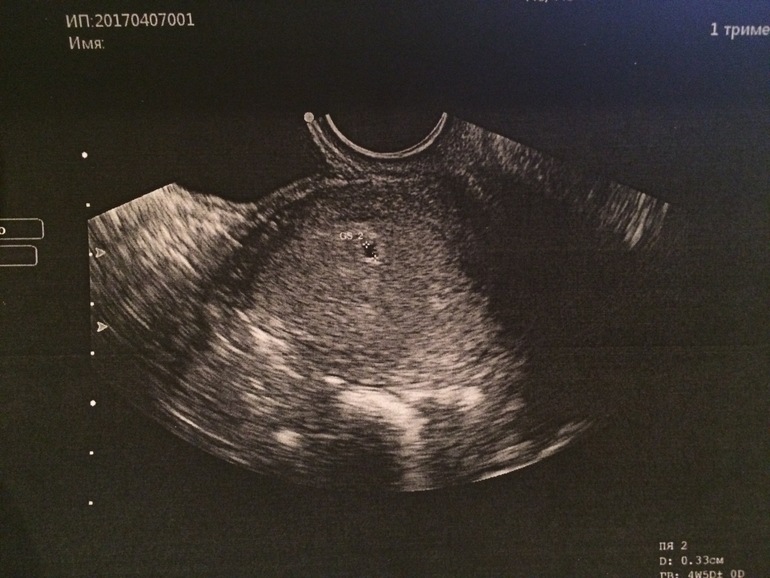

Всем привет. Б на данный момент срок 5 недель 4 дня. Была на приёме, сделали УЗИ 07.04. Сказали 17-18 приходить встать на учёт, можно ли будет ровно в 6 недель увидеть сердцебиение? Очень боюсь зб